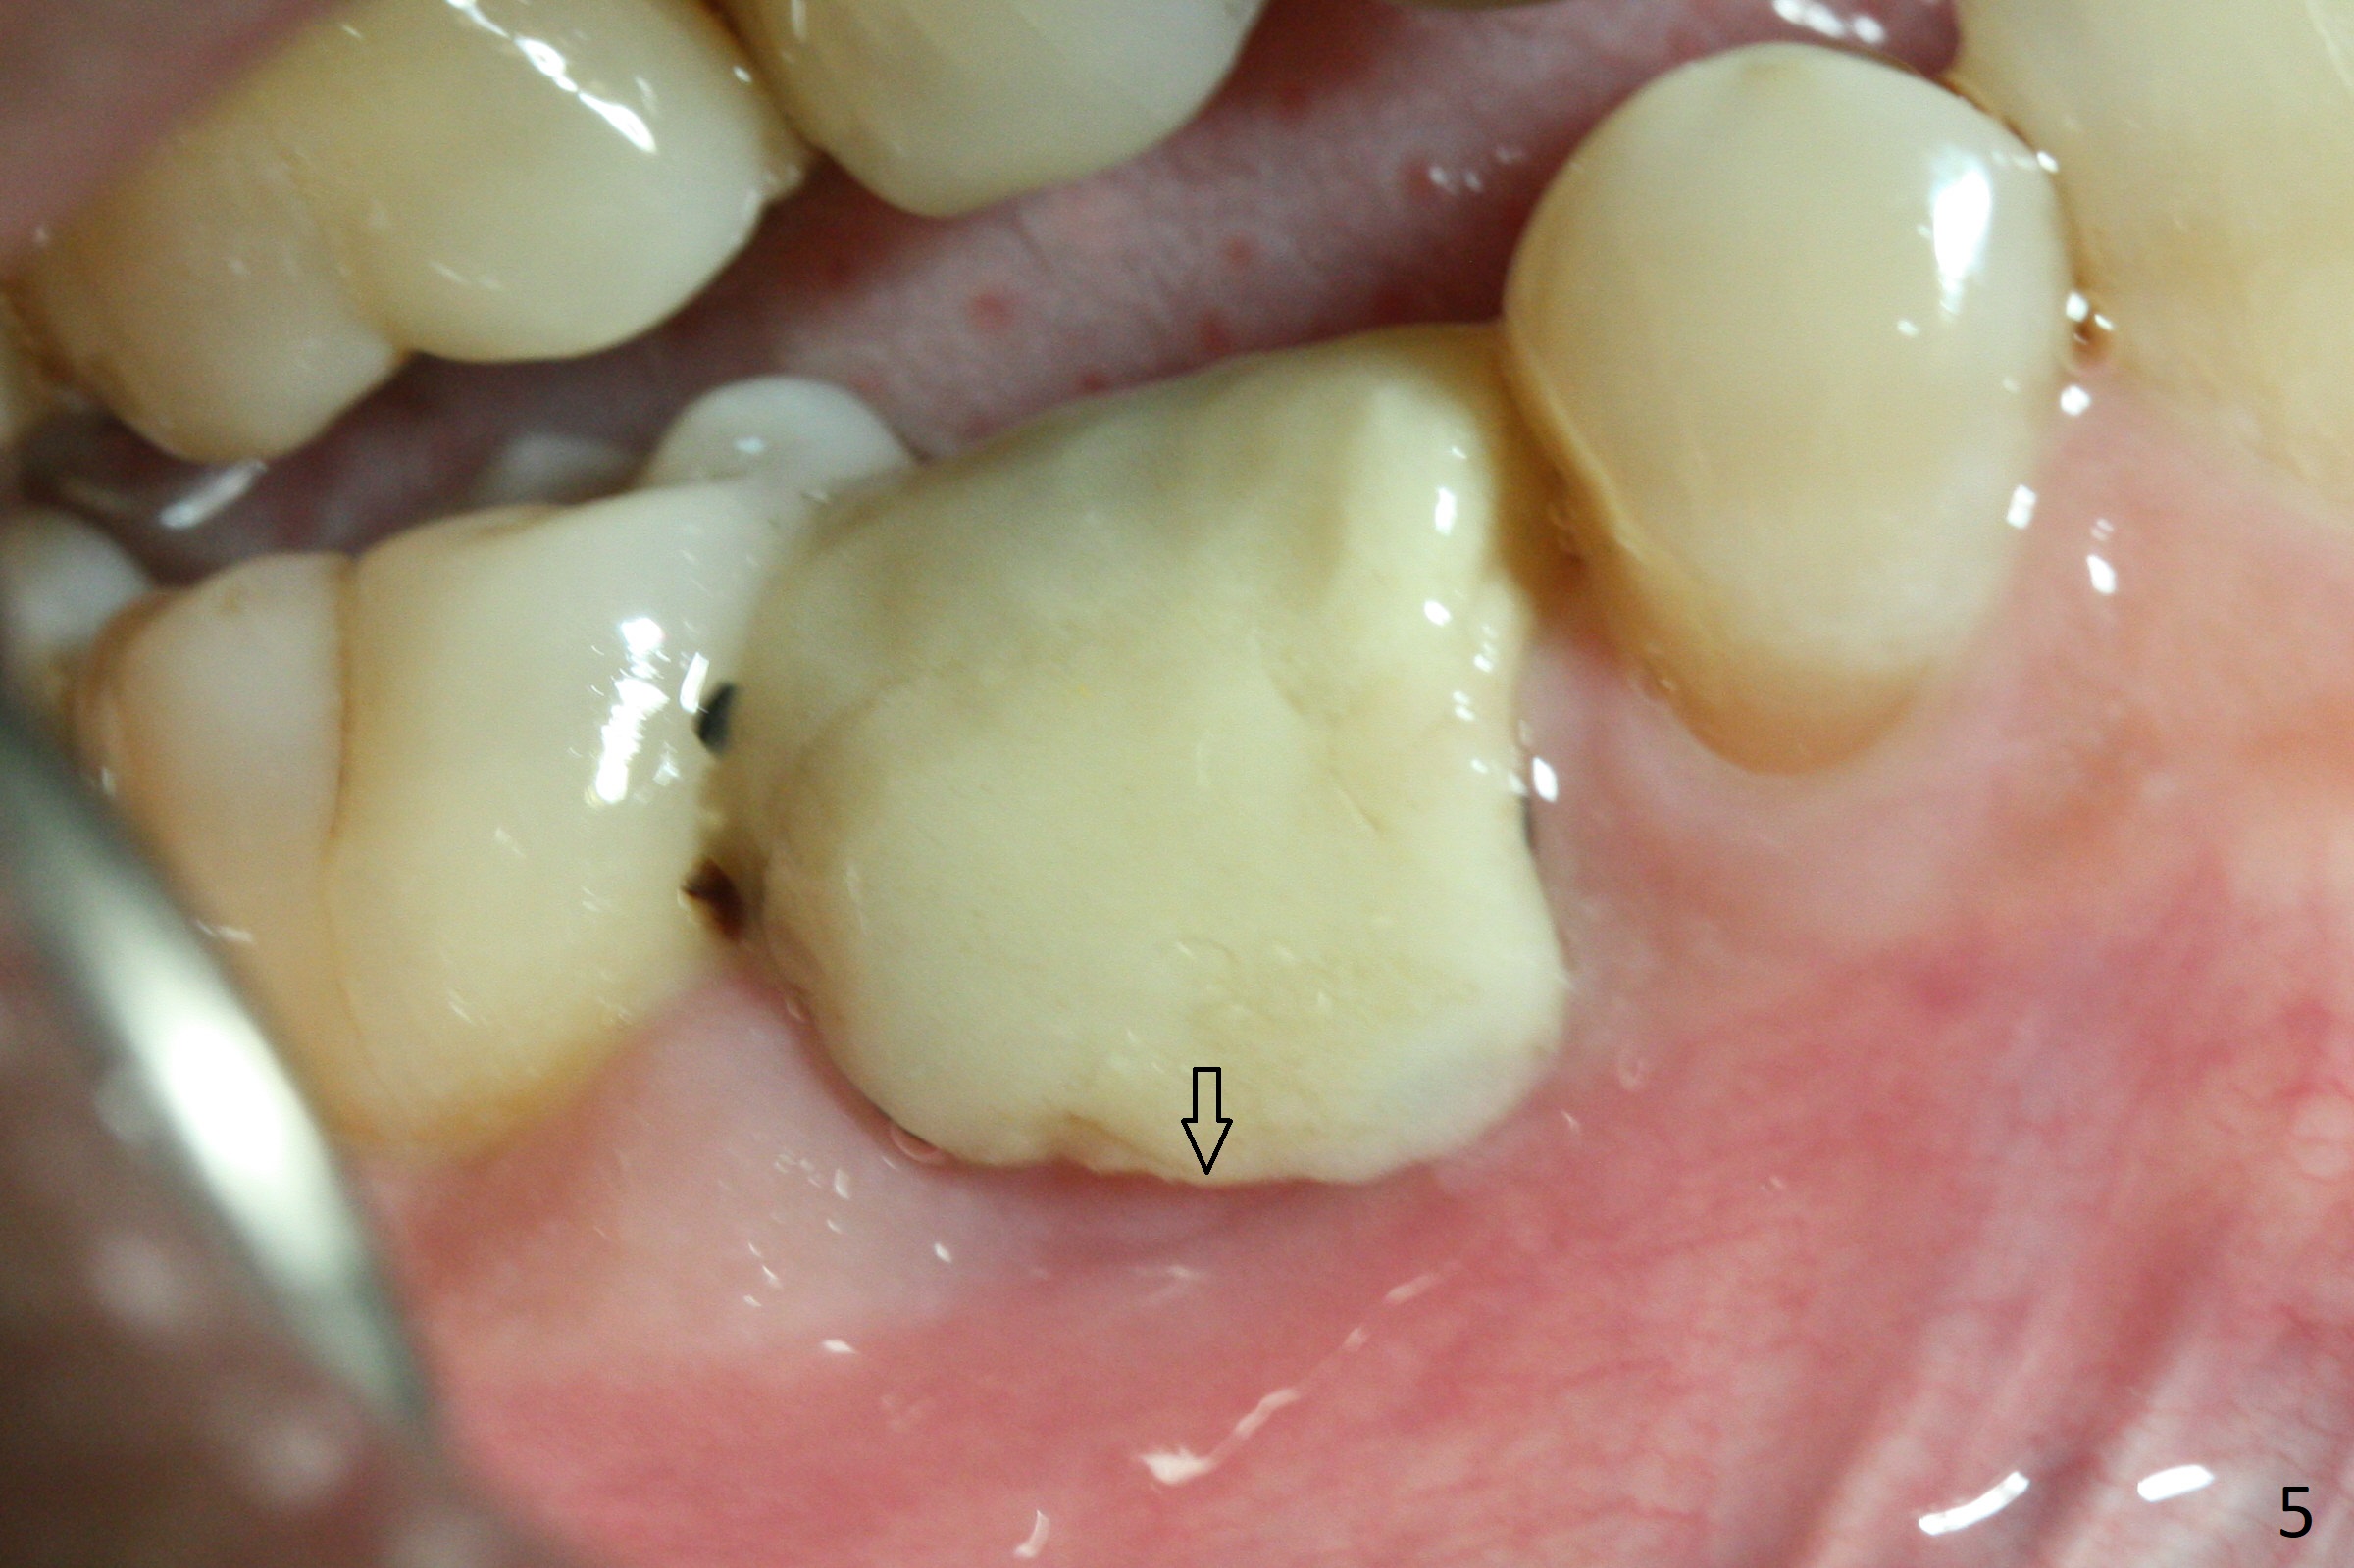

The retained deciduous tooth (lower right 2nd molar, Fig.1 T) has buccal apical infection and recession. After extraction, the initial depth of osteotomy is 11 mm over the flat socket bottom (Fig.2) without visible Mental Loop. Following 3.8 mm Magic Drill for 11 mm, a 4x11 mm dummy implant is placed partially due to hard bone; it appears that the apical osteotomy (Fig.3 yellow outline) overlaps the Mental Loop (red dashed line). For safety, a 4x9 mm IBS implant is placed with insertion torque 40 Ncm; a 5x5.7(4) mm abutment is immediately placed for an immediate provisional to cover the large socket and keep Vera graft in place (Fig.4 *). There is no postop paresthesia, probably due to the fact that the osteotomy is lingual to the Mental Loop. The provisional remains in place 7 days postop; its margin (Fig.5 arrow) covers the socket. The margin of the provisional is trimmed 1 month postop. Impression is taken nearly 3 months postop (Fig.6). The buccal plate looks atrophic 3 months postop (Fig.7 (immediately before cementation)), although there is no sign of periimplantitis. In the future, insert the immediate provisional inside of the buccal gingiva to make the buccal gingiva look bulky instead of buccal to it (Fig.5). The second drawback of placing an implant at the deciduous tooth area is that the crown is wide mesiodistally if orthodontic treatment is not rendered. Although there is lower anterior crowding, the patient declines orthodontic treatment. The bone density around the implant increases 7 months post cementation (Fig.8 *). The higher density bone seems to extend coronally 1 year 7 months post cementation (Fig.9). The dense bone apparently extends toward the abutment as well 3 years 5 months post cementation (Fig.10 curved arrows).